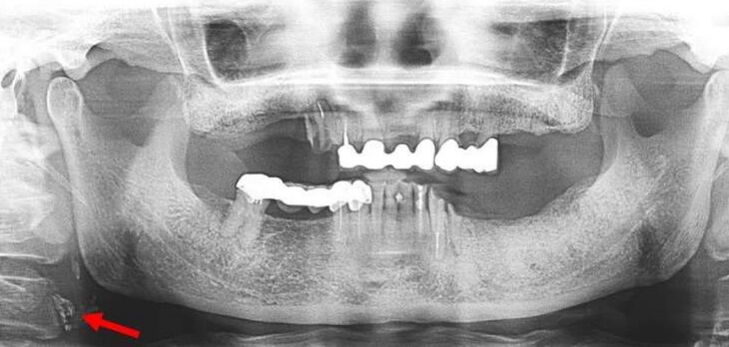

42.附圖中箭頭所指的骨折屬於下列何者? (A)condylar neck (B)diacapitular (C)subcondylar (D)sigmoid notch